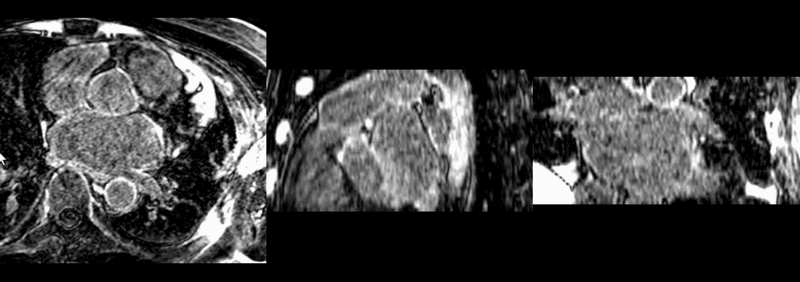

Experiment 3: Registration of Atrial Fibrillation Pre and Post Treatment

After affine registration.

After BSpline registration.

After unconstrained diffeomorphic demons.